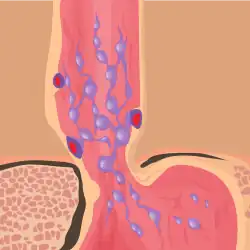

Esophageal varices are extremely dilated sub-mucosal veins in the lower third of the esophagus.[1] They are most often a consequence of portal hypertension,[2] commonly due to cirrhosis.[3] People with esophageal varices have a strong tendency to develop severe bleeding which left untreated can be fatal. Esophageal varices are typically diagnosed through an esophagogastroduodenoscopy.[4]

Normal portal pressure is approximately 9 mmHg compared to an inferior vena cava pressure of 2–6 mmHg. This creates a normal pressure gradient of 3–7 mmHg. If the portal pressure rises above 12 mmHg, this gradient rises to 7–10 mmHg.[5] A gradient greater than 5 mmHg is considered portal hypertension. At gradients greater than 10 mmHg, blood flowing through the hepatic portal system is redirected from the liver into areas with lower venous pressures. This means that collateral circulation develops in the lower esophagus, abdominal wall, stomach, and rectum. The small blood vessels in these areas become distended, becoming more thin-walled, and appear as varicosities.

Varices can also form in other areas of the body, including the stomach (gastric varices), duodenum (duodenal varices), and rectum (rectal varices). Treatment of these types of varices may differ. In some cases, schistosomiasis also leads to esophageal varices.

Dilated submucosal veins are the most prominent histologic feature of esophageal varices. The expansion of the submucosa leads to elevation of the mucosa above the surrounding tissue, which is apparent during endoscopy and is a key diagnostic feature. Evidence of recent variceal hemorrhage includes necrosis and ulceration of the mucosa. Evidence of past variceal hemorrhage includes inflammation and venous thrombosis.